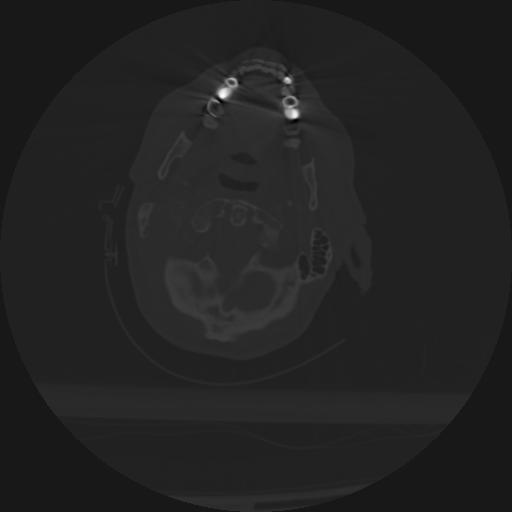

22 ANGIO,CE,Vol,0.5,ANGIO,,